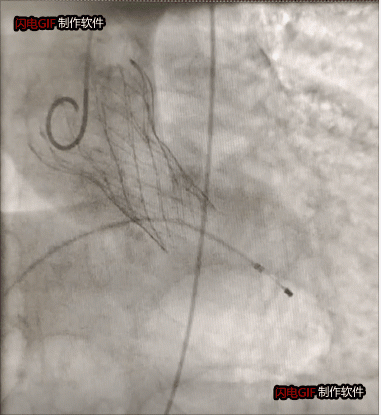

瓣膜植入后反流完全消失

整個(gè)手術(shù)過(guò)程僅1小時(shí),瓣膜釋放后主動(dòng)脈瓣反流完全消失,舒張壓迅速由14上升到60mmHg左右。目前患者已順利康復(fù)出院。